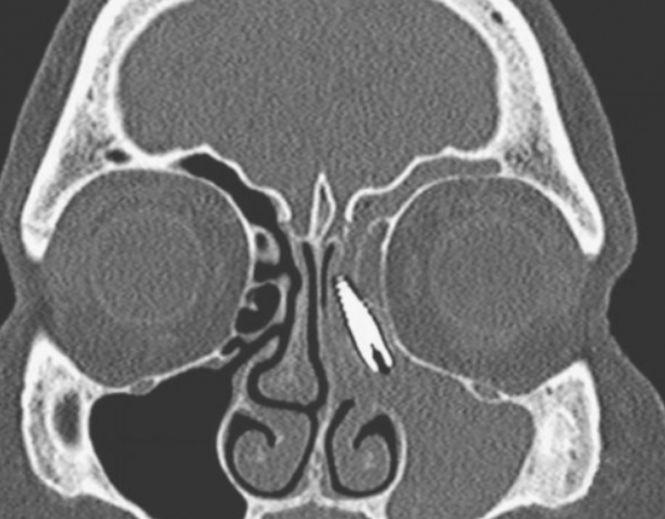

Doi ani a avut dureri crunte în nas. Nu a mai suportat și a mers la spital. Ce avea acolo i-a speriat pe doctori